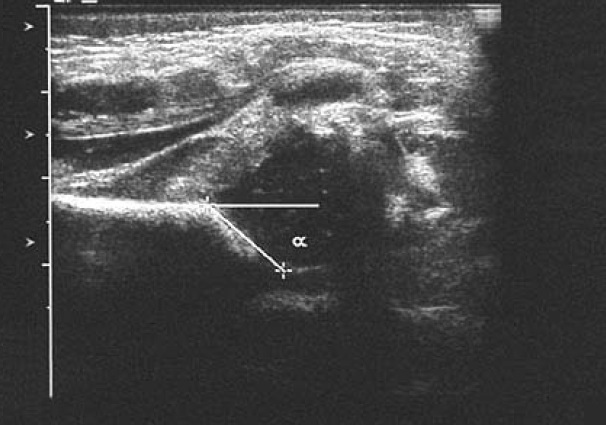

normal alpha angle

greater than 60 deg

(pic is abnormal)